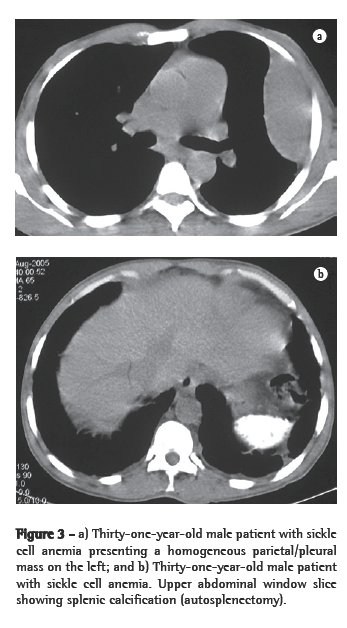

Of the six patients evaluated, four presented lower paravertebral masses. In three cases, the masses were bilateral and relatively symmetric, and, in one, the mass was unilateral (on the right). Regarding the content of the masses, the presence of adipose tissue was confirmed in three patients, and, in one of them, the quantity of adipose material was quite significant. In one patient, the masses were homogeneous, with dense soft parts (Figures 1a, 1b, 2a and 2b).

The remaining two patients each presented a parietal pleural mass, both on the left, with no evidence of paravertebral involvement. In one of them, the mass was homogeneous (Figures 3a and 3b), and, in the other, there was associated bone reaction.

Thoracic involvement in EMH is rare.(1,5) When it occurs, it usually manifests as round, lobulated masses, with dense soft parts in the posterior mediastinum, being more common in the lower paravertebral regions.(1,2,4,5,9) Occasionally, those masses can appear in the anterior mediastinum or in the pleura.(4) Pleural effusion has been reported.(2,13) Four of our patients presented lower paravertebral masses, and two presented parietal pleural masses.

Radiographically, intrathoracic EMH usually presents as multiple paravertebral masses, with dense soft parts, usually bilateral, lobulated, with well-defined borders, and without accompanying calcifications or bone erosion.(1,4,5,9) This is important for the differential diagnosis of paravertebral neurofibromas, which usually have accompanying bone alterations.(4,10) However, evidence of bone lesions related to the underlying disease is a common finding. On chest X-rays, such masses usually present an aspect of lobulated, double-contour cardiac silhouette in frontal view, as well as an aspect of a lobulated mass projected over the lower vertebral bodies in profile.(13)